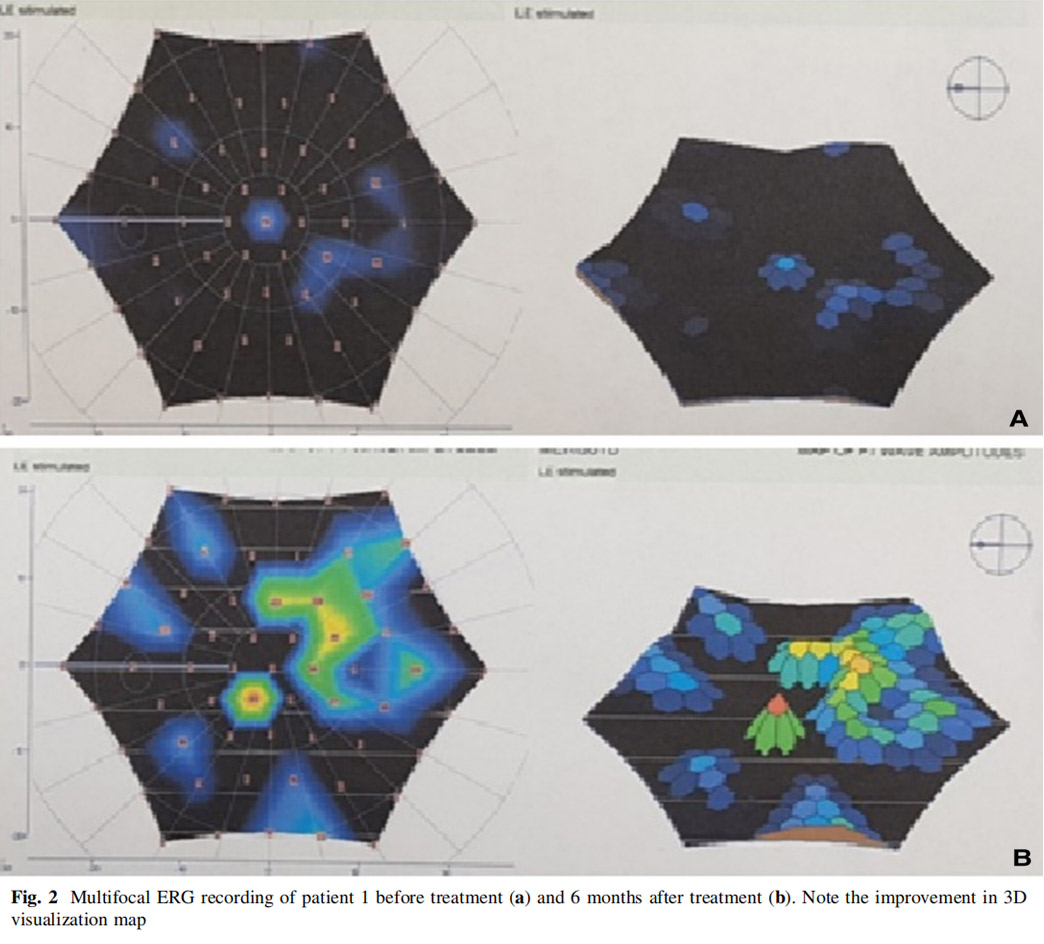

患者1:一名52歲男性,因糖尿病視網膜病變接受了雙側全視網膜氬激光光凝術,在過去2年中一直患有進行性視力喪失,AD-MSCs治療前右眼視力10/200,左眼視力2英尺(約0.6米)處的手部運動(HM),雙眼視神經蒼白,視野檢查顯示雙眼中央島狀結構,左眼較小,mfERG顯示雙眼振幅降低,OCT和RNFL均顯示雙眼黃斑、脈絡膜和神經纖維層變薄。

患者左眼接受AD-MSCs治療,6個月后視力提高至2米處數手指(CF)水平,視野中央島狀結構擴大,如圖1所示,左眼mfERG顯示改善(圖2),脈絡膜厚度從273μm增加至318μm(圖3),黃斑厚度和RNFL沒有變化。